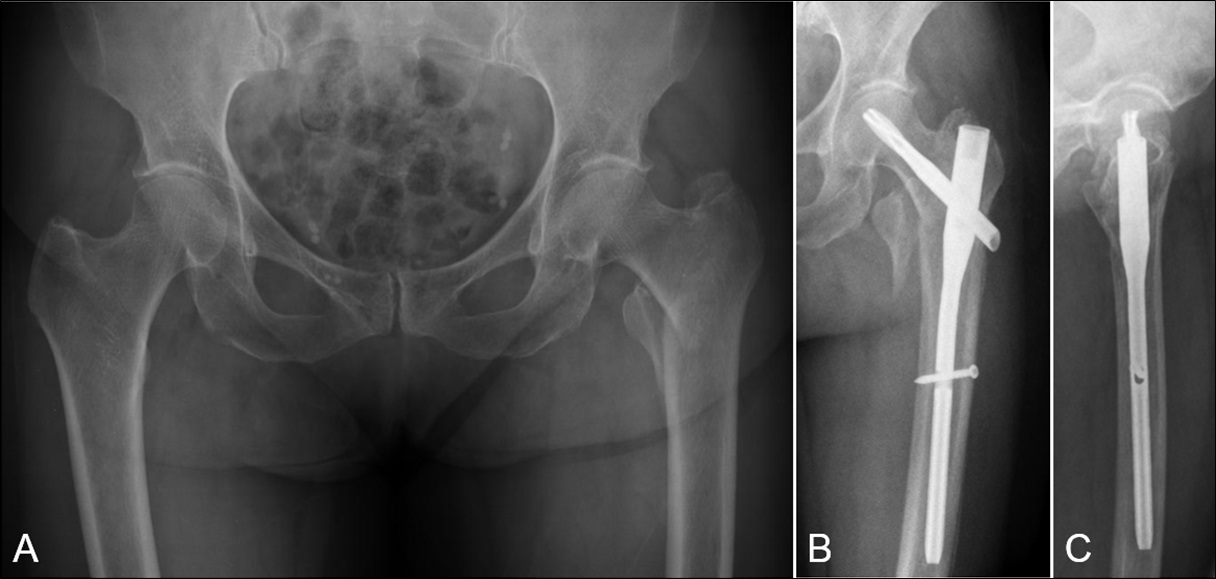

Penetración de la cortical anterolateral en fracturas de fémur proximal tratadas con clavos endomedulares cortos Reporte de dos casos. [Penetration of anterior-lateral cortex in proximal femur fractures treated with short intramedullary nails Report of two cases].